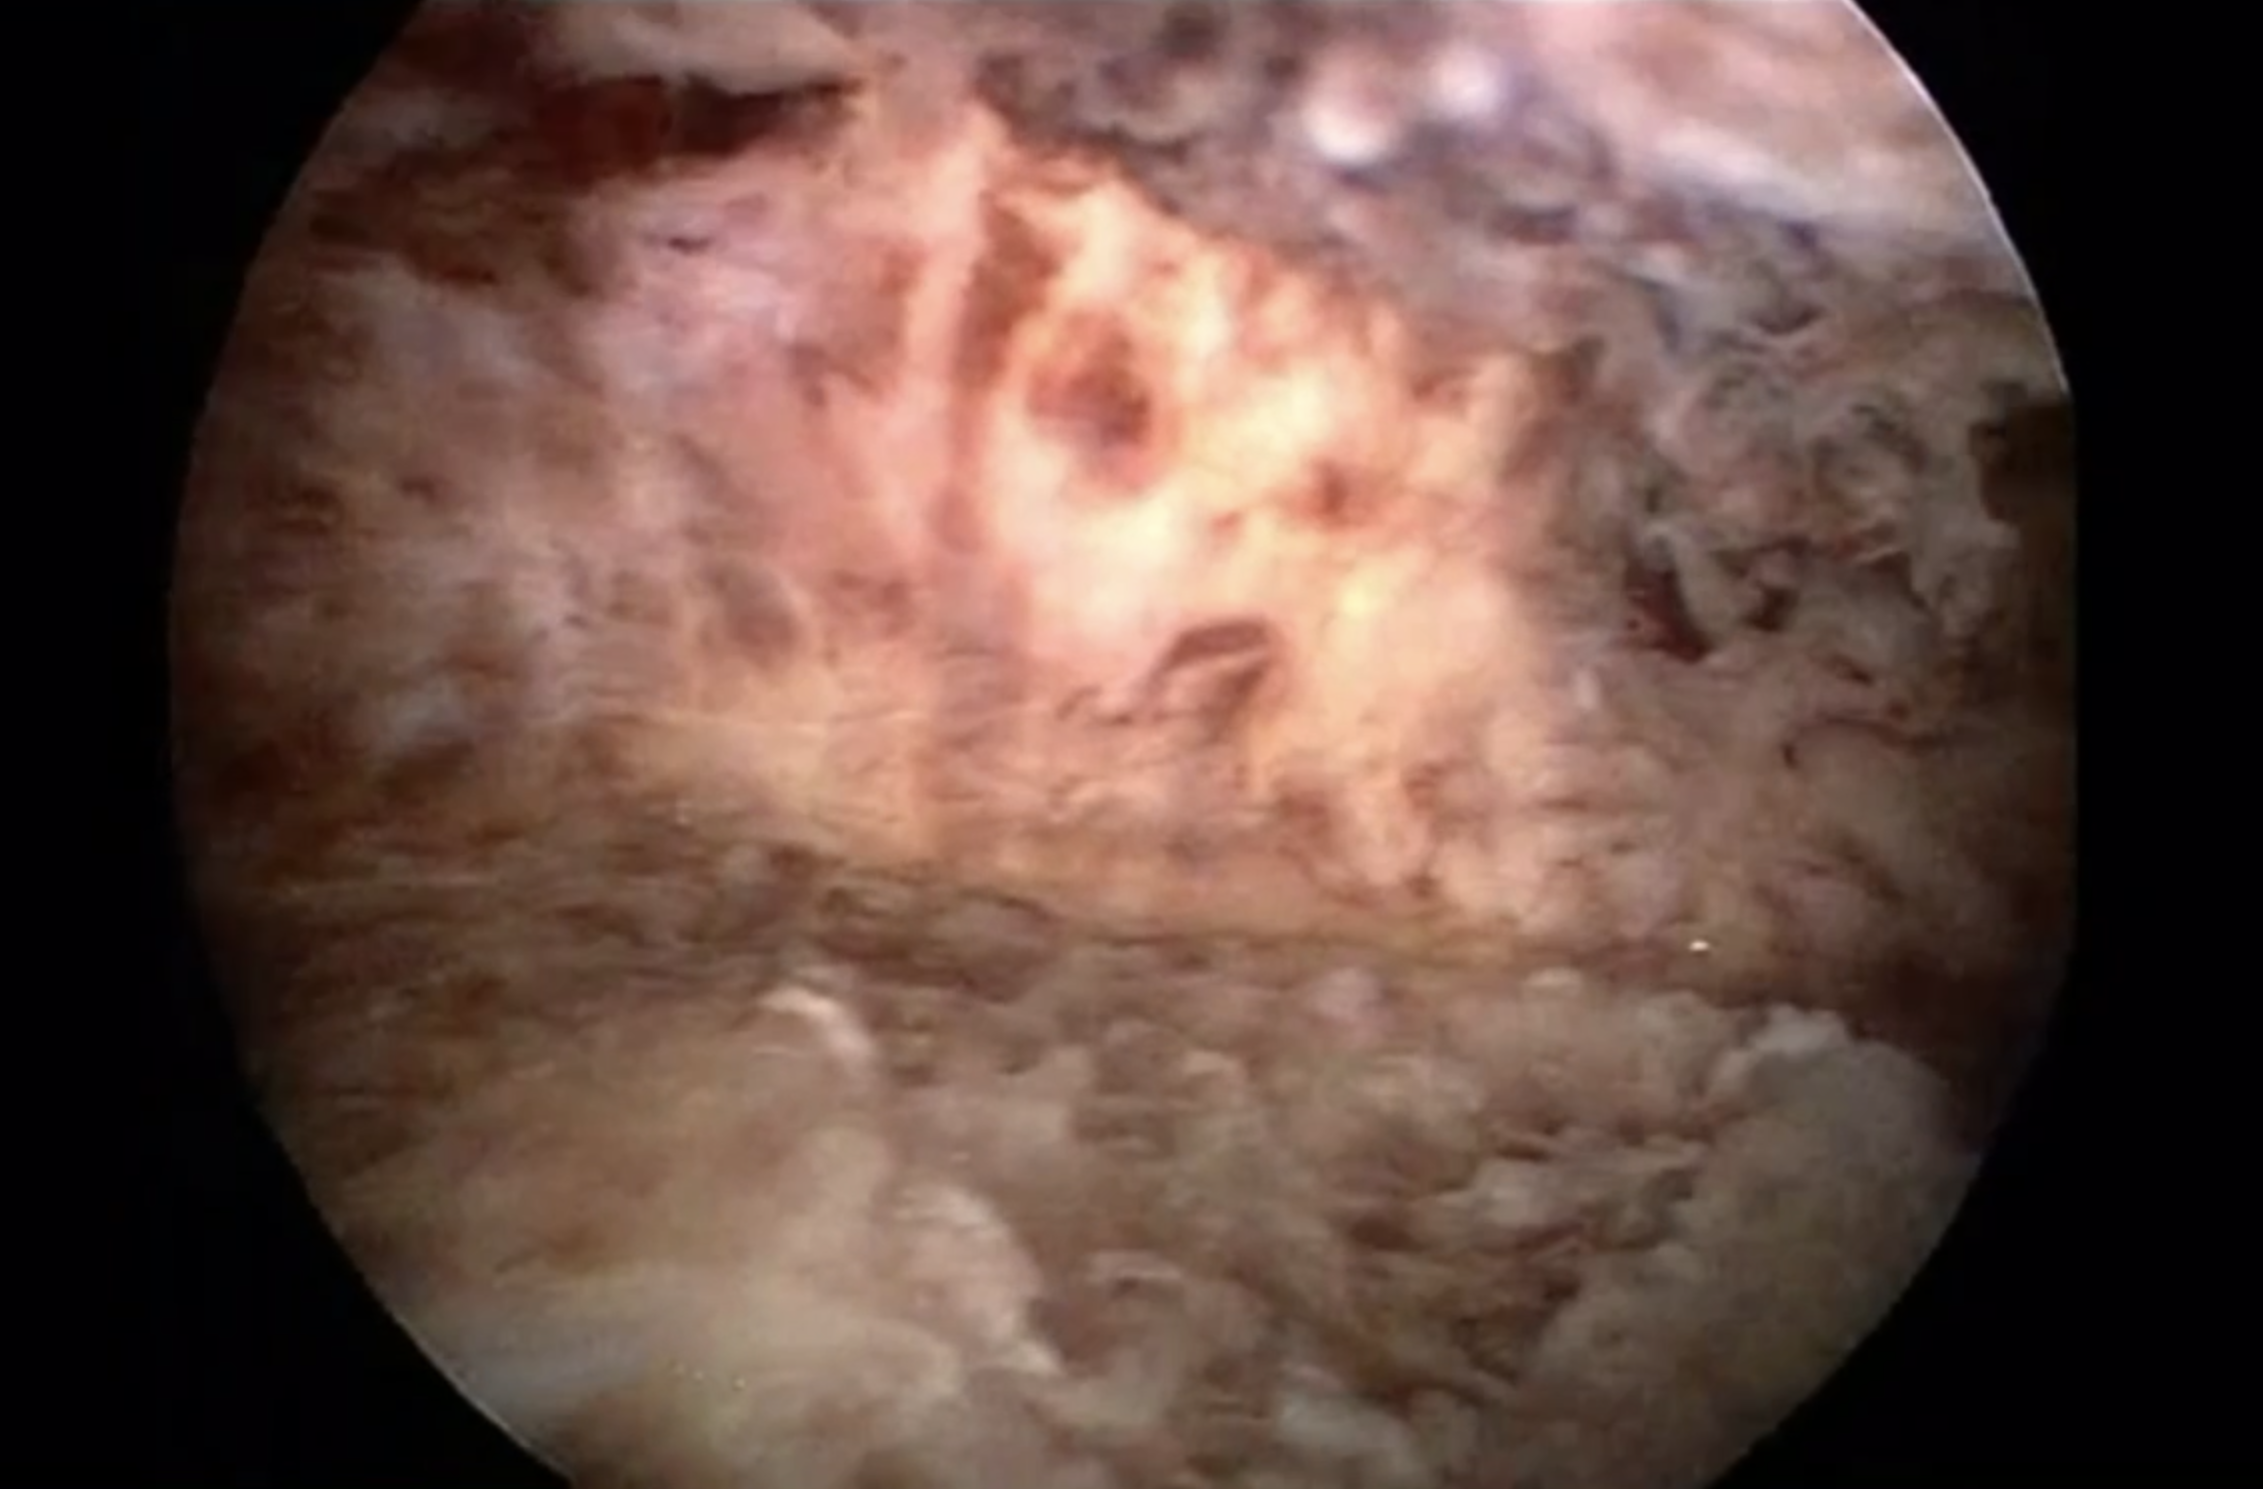

Schleimhaut vor Novasure Schleimhaut nach Novasure

Das Verfahren besteht in der dauerhaften Entfernung der Gebärmutterschleimhaut (Endometrium) durch Hochfrequenzstrom, durch die zukünftige Blutungen reduziert bzw. beseitigt werden. In Narkose wird ein dreieckiges Goldnetz in der Gebärmutterhöhle entfaltet. Durch eine Aktivierung von Hochfrequenzstrom für durchschnittlich ca. 90 Sekunden wird die Schleimhaut verschorft. Danach wird das Netz wieder entfernt und die Operation ist beendet.